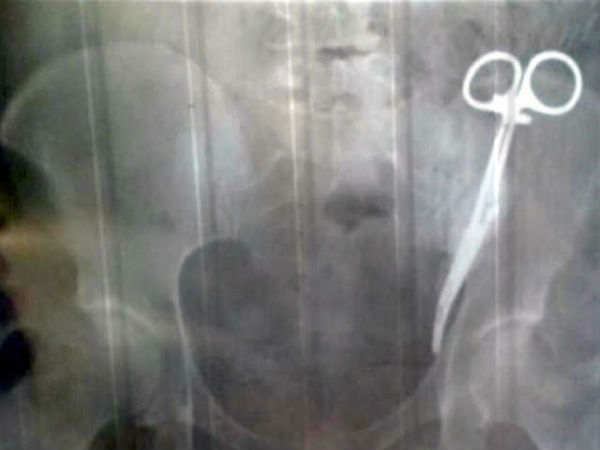

23 வருஷத்துக்குமுன் ஆபரேஷனில் கத்தரிக்கோலை வயிற்றுக்குள் மறந்து வைத்த டாக்டர்... இப்ப எடுத்துருக்காங

23 ஆண்டுகள் வயிற்றுவலியால் துடித்த பெண்: உள்ளே இருந்தது பற்றி தான் இந்த கட்டுரையில் பார்க்கப் போகிறோம். அது பற்றிய தொகுப்பு தான் இது.

23 வருஷத்துக்குமுன் ஆபரேஷனில் கத்தரிக்கோலை வயிற்றுக்குள் மறந்து வைத்த டாக்டர்... இப்ப எடுத்துருக்காங்க... அந்த கொடுமையைப் பற்றித் தான் இந்த தொகுப்பில் நாம் பார்க்கப் போகிறோம்.

அதிர்ச்சியளித்த எக்ஸ்ரே

எலீட்டாவுக்கு எக்ஸ்ரே பரிசோதனை செய்த சிறப்பு மருத்துவருக்கு தன் கண்களையே நம்ப இயலவில்லை. எலீட்டாவின் வயிற்றுக்குள் கத்தரி ஒன்று இருந்தது. எக்ஸ்ரே எடுக்கும் அறைக்குள் எலீட்டா கத்தரிகோலை தவறுதலாக எடுத்துச் சென்றிருக்கூடும் என்று நினைத்தார். ஆனால், உண்மையில் வயிற்றினுள்ளேதான் கத்தரி இருந்தது.

யார் வைத்தது?

வயிற்றினுள் கத்தரிகோல் எப்படி வந்திருக்கக்கூடும் என்று மருத்துவர்கள் கேட்டபோது எலீ்ட்டாவுக்கு என்ன சொல்வதென்று புரியவில்லை. தனக்கு 23 ஆண்டுகளுக்கு முன்பு சிசேரியன் அறுவை சிகிச்சை செய்யப்பட்டது என்று கூறினார். அப்போது அறுவை சிகிச்சை செய்த மருத்துவர் கத்தரியை மறந்துபோய் எலீட்டாவின் வயிற்றுக்குள் வைத்துவிட்டது தெரிய வந்தது. 23 ஆண்டுகள் தேவையில்லாமல் வேதனைப்பட்டதற்கு எலீட்டாவுக்கு நஷ்ட ஈடு வழங்கவும் சம்மந்தபட்ட மருத்துவர் மீது நடவடிக்கை எடுக்கவும் பரிந்துரைக்கப்பட்டுள்ளது.